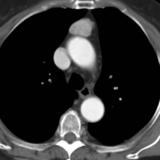

Case 8c Thymoma CT

Date: 03/27/2009

Views: 15480